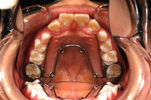

叢生(そうせい)・がたがた・永久歯萌出スペース不足

主訴:不正咬合の恐れ・2┴2の萌出スペース不足

年齢:8y8m

診断:叢生

装置・期間:

第一期治療 上下顎拡大装置(クアッドヘリックス・バイヘリックス)+上顎マルチブラケット装置 3年7カ月間(9y0m~2y7m)

第二期治療 上下顎マルチブラケット装置 1年間(12y11m~13y11m)

保定 上下顎保定装置 2年間以上

治療費:第一期治療 矯正基本料400,000円+処置料3,000~6,000円×27回(別途消費税)

第二期治療 矯正基本料400,000円+処置料3,000~6,000円×12回(別途消費税)

保定装置料 50,000円(別途消費税)